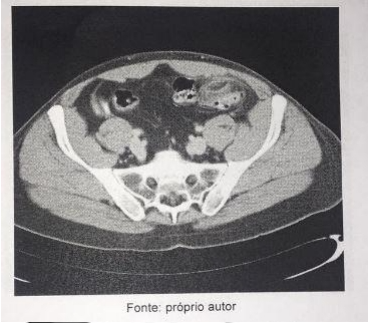

Homem, 56 anos de idade, há 3 dias com dor abdominal persistente. Conta que a dor se localiza na fossa ilíaca esquerda, em facada, de moderada a forte intensidade, comprometendo suas atividades diárias, além de hiporexia pela dor. Exame clínico: pressão arterial = 110 x 80 mmHg, frequência cardíaca = 88 batimentos/minuto, frequência respiratória = 18 movimentos/minuto, temperatura axilar = 36,9°C; dor à palpação da fossa ilíaca esquerda, com defesa na região. Exames complementares indicam uma leve leucocitose neutrofilica, com aumento da proteína C reativa. Realizou o exame de imagem a seguir (imagem 1). Assinale a conduta imediata indicada para o caso: